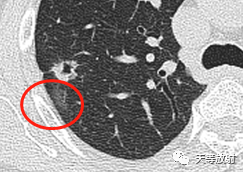

这个层面出现囊腔+实性结节,囊壁较厚。